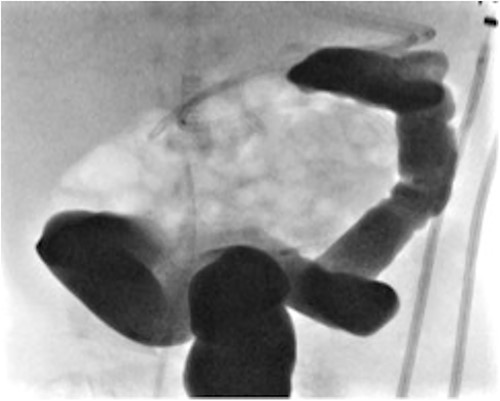

At elective ileostomy closure 2 months later, a colonic stricture was found 5 cm distal to mucous fistula, which was resected. Saline was instilled distal to the excised colonic stricture, which did not progress suggesting further distal obstruction. The decision was made to defer stoma closure at this stage. Subsequent colonoscopy revealed normal distal colon up to the level of the distal transverse colon at which point the colon was completely occluded in a blind ending pouch and on probing with a guide wire no lumen was found. Atresia was confirmed with contrast enema (Fig. 3). At 8 months of age, he underwent laparotomy and resection of a 10 cm section of transverse colonic atresia. Histology reported narrowing of the transverse colon, focal granulation tissue, and mucosal web formation. His recovery and subsequent follow-up have been uneventful.

Contrast enema for case 2 showing complete failure of passage of contrast into distal transverse colon.